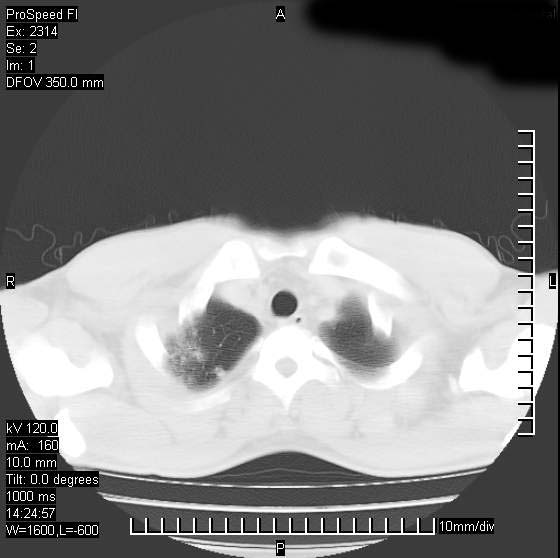

男性,再生障碍性贫血,入院前发热10天,最高40c,右侧胸痛,外院ct示右上,中肺边缘模糊的球性影(就是我现在图中标示的范围),考虑炎症,在我院使用头孢呋辛,洛美沙星10天,高烧消退,自感下午稍有发热,但今天ct示右上,中肺病灶明显扩大,还是考虑炎症,看其中的球型影是否霉菌感染??,是否能排除结核?

右肺中叶外侧段病变,上缘界限不清,下缘锐利,以段性发病为主,内见巨大空洞及空洞内容物,结合病史首先考虑:化脓性肺炎。不除外霉菌感染!

片状高密度影内见空洞影,内可见球形软组织密度影,并有新月征,考虑霉菌感染.